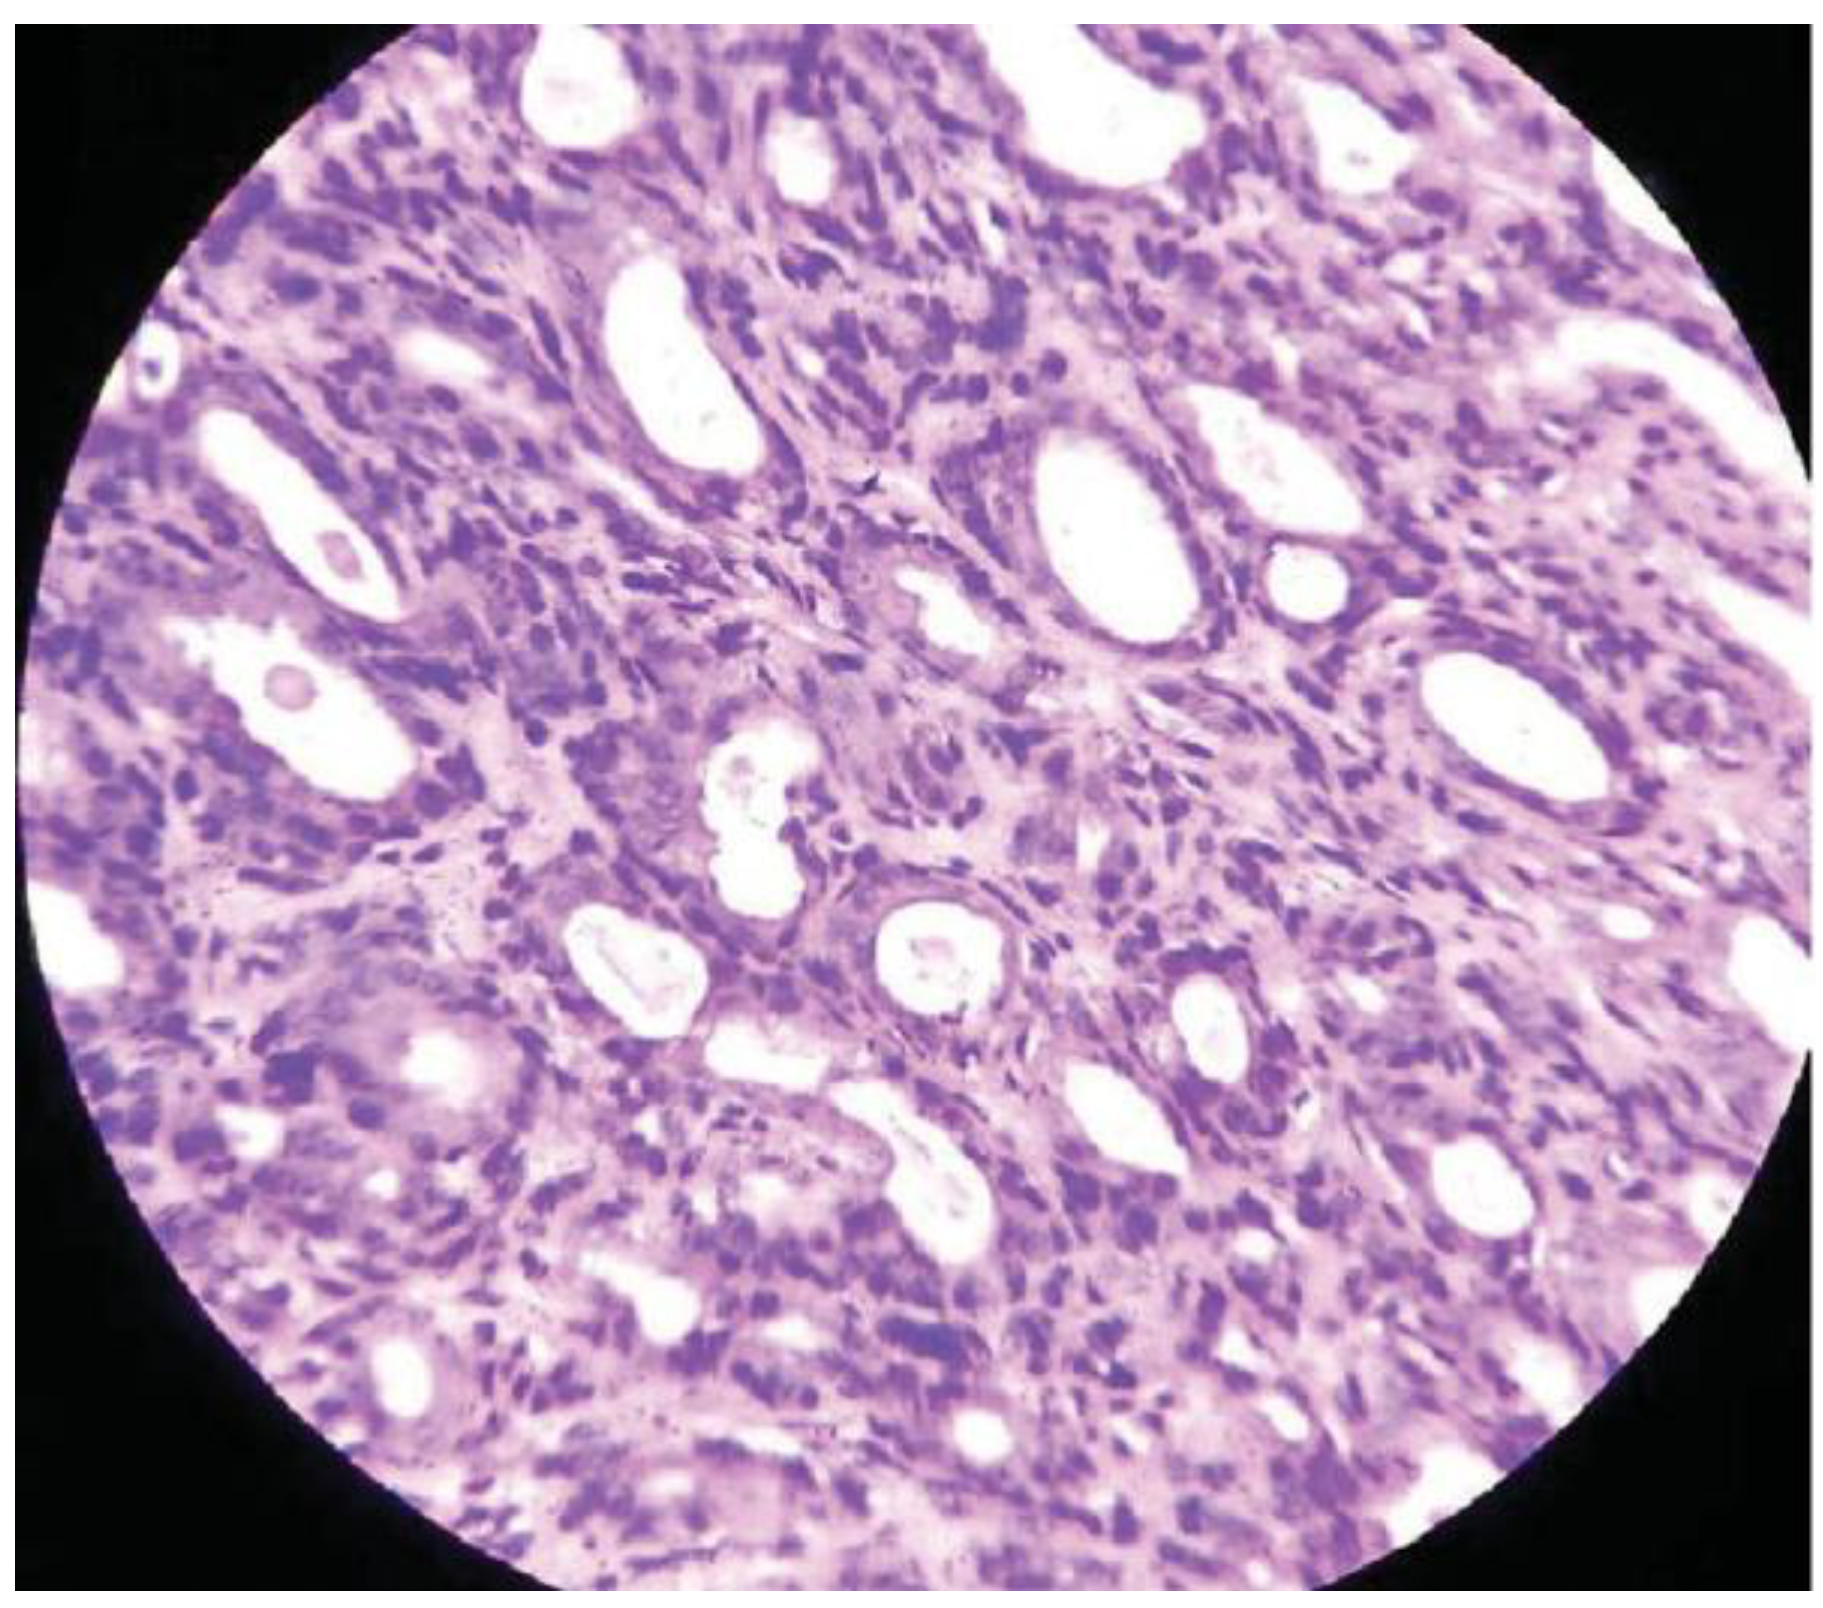

Basal Cell Adenoma of Retromolar Region from Minor Salivary Gland Origin in a 45-Year-Old Female: A Case Report

:Case Presentation